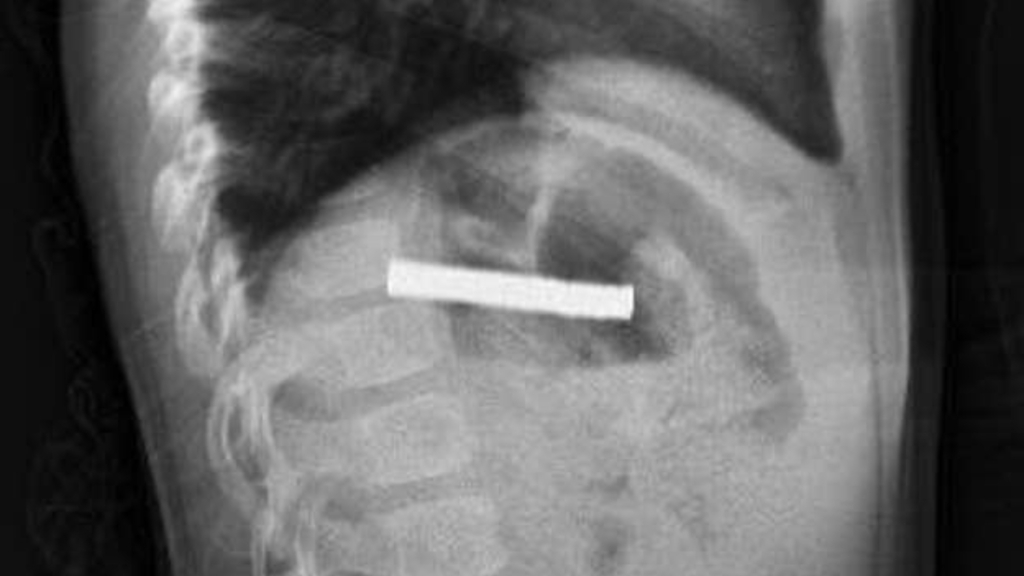

Erzurum’da meydana gelen ilginç bir olayda, bir çocuk evde bulunan 19 mıknatısı yuttu.

Çocuğun rahatsızlandığını fark eden ailesi, hemen hastaneye başvurdu.

BOĞAZINDAN 19 ADET MIKNATIS ÇIKARILDI

Çocuk, daha sonra Elazığ’a sevk edildi.

Fırat Üniversitesi Çocuk Gastroenteroloji Hepatoloji ve Beslenme Bilim Dalı Başkanı Prof. Dr. Yaşar Doğan, küçük hastanın yemek borusuna yapışmış 19 mıknatısı endoskopik yöntemle başarıyla çıkardı.

Mıknatısların uzun süre yemek borusunda kalması nedeniyle, yemek borusu ve mide girişinde bazı zedelenmeler meydana geldi. Ancak çocuğun sağlık durumunun iyi olduğu ve taburcu edildiği bildirildi.